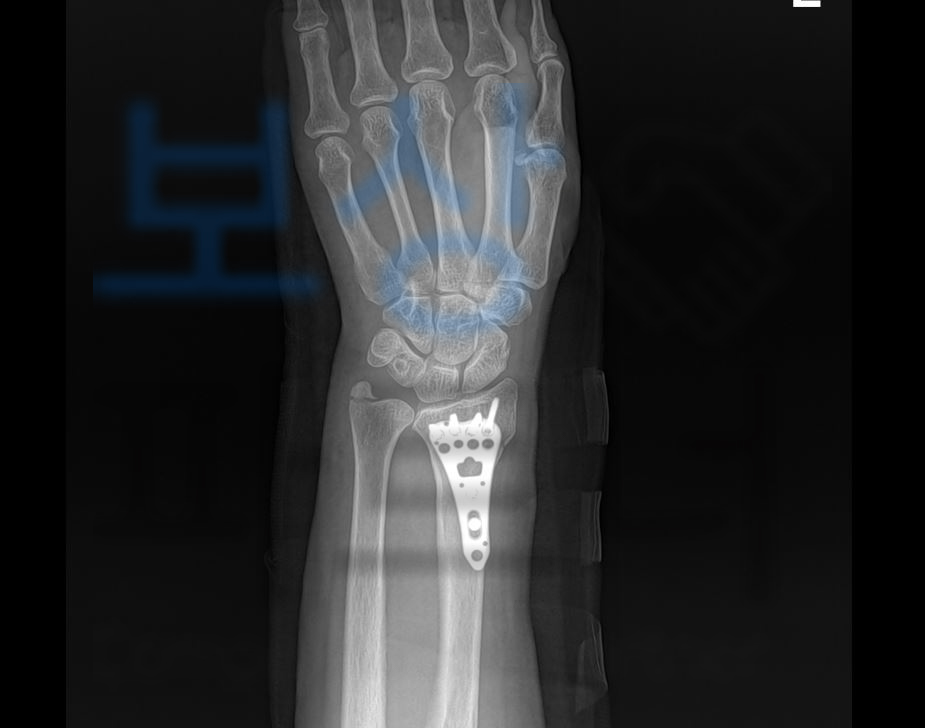

손목 요골골절된 부위의 조각난 골편을 맞추기 위해 관혈적 정복 및 금속판 내고정술을 시행하셨고 최소 6주 이상의 요양이 필요하셨죠.

요골 원위부 골절

진단을 받으셨죠.

환자분은 무려 요골골절 뚜렷한 장해 10%지급율에 해당하셨죠. 보상파트너는 환자의 장해에 대한 적정성을 증명하기 위해 손해사정서 및 증빙자료를 각 보험사에 송부하였습니다. 물론 보험사에서도 조사관을 배정하여 내부자문 및 의료자문까지 시행하며 보험금 적정성을 조사하였는데요, 장해율에 과대평가되었다는 주장을 해왔지만 보상파트너의 적절한 대응 끝에 처음 청구한 10%지급율 모두 인정받을 수 있었습니다!

후유장해 보험금 2,200만 원입니다.